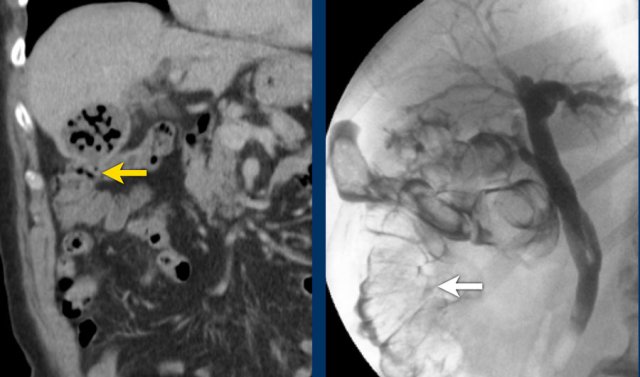

Bouveret syndrome

In rare cases of duodenal fistulisation, a large gallstone may get “stuck” during a longstanding fistulisation process.

Due to secondary inflammatory and fibrous tissue, this may eventually lead to stenosis and obstruction of the duodenum.

This special situation is called “Bouveret syndrome” and its main clinical feature is gastric outlet obstruction (fig).

Although rare, it is very important to make the correct diagnosis, because cholecystectomy is very dangerous and should be avoided.

If the stone cannot be removed endoscopically, the best solution is a gastrojejunostomy.

Images of an elderly lady, presenting with gastric retention and vomiting.

CRP was 55, but was documented to be 160 a few days earlier.

US shows a large stone in a gallbladder filled with debris-like material, and an irregular wall.

The stomach is dilated and there is remarkable wall thickening of the duodenum (arrowheads) and surrounding inflammation (asterisk).

Gastroscopy was done for suspected malignancy, but biopsy only revealed inflammation.

Continue with the CT.

CT confirms the diagnosis of Bouveret syndrome.

Percutaneous gallbladder drainage relieved the symptoms of gastric retention.

One year later, the stone apparently managed to evacuate to the duodenal lumen, and she developed a classic gallstone-ileus as yet, which was operated successfully.